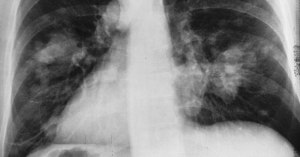

Le cancer du poumon est l’un des principaux cancers qui sévissent en France mais également l’un des plus meurtriers. En 2017, sur les 49 000 personnes atteintes d’un cancer du poumon, 31 000 en sont mortes. Ce nouveau traitement découvert par les chercheurs pourrait bien sauver de nombreuses vies.